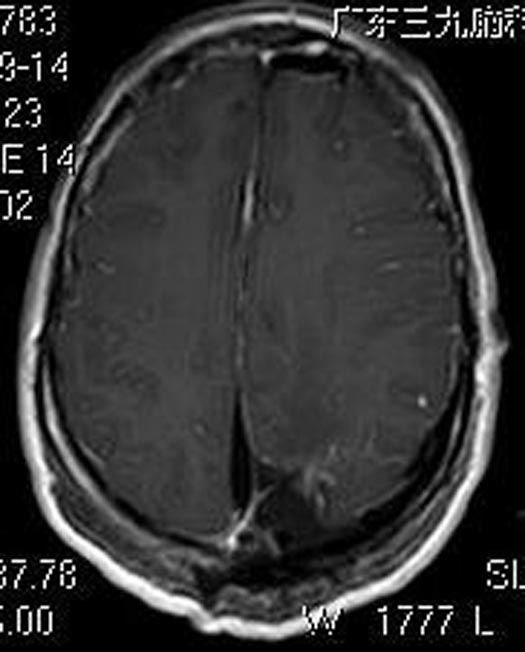

吴小姐4个月前出现反复头痛,伴有双眼视物模糊,偶有右耳耳鸣,无明显头痛等不适,当地医院头颅CT检查提示“左侧顶枕叶占位,考虑脑膜瘤”;广东三九脑科医院头颅MR检查显示:左侧顶枕部占位性病变,范围约7.1cm×6.8cm×5.9cm;进一步行头颅CTA检查提示:其内血供丰富。

由鲁明主任主刀,在全麻下行左侧顶枕部巨大脑膜瘤切除术,术中见肿瘤呈灰褐色,质中,边界较清,血供丰富,显微镜下分块全切肿瘤,手术过程顺利。术后吴女士头痛症状明显较前好转,四肢肌力、肌张力正常,康复出院。术后病理结果提示:脑膜皮细胞型脑膜瘤 WHO I级。